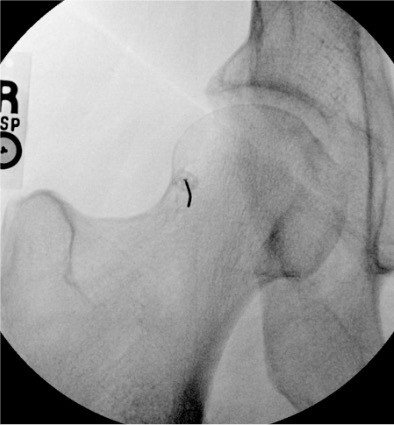

| Hip | 10–20 mL (MR arthro: 12–15 mL) | Fluoroscopy | Anterior approach | Femoral head-neck junction; confirm intra-articular with ring sign — contrast outlines femoral head circumferentially; iliopectineal bursa communicates with joint in ~15% (acceptable) |

Hip

Needle placementPost-injection